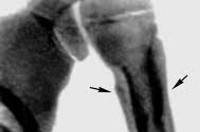

Основанием для постановки диагноза гнойный периостит являются характерные симптомы и данные дополнительных исследований. По анализам крови определяется острое воспаление. Рентгенологическая картина на ранних стадиях может быть нормальной. В последующем выявляется тень обызвествленных периостальных наложений, отделенных от коркового вещества прозрачной полоской. Через некоторое время участки обызвествления сливаются с костью, образуя картину асимметричного утолщения кости. При корковых абсцессах обнаруживаются деструктивные очаги.